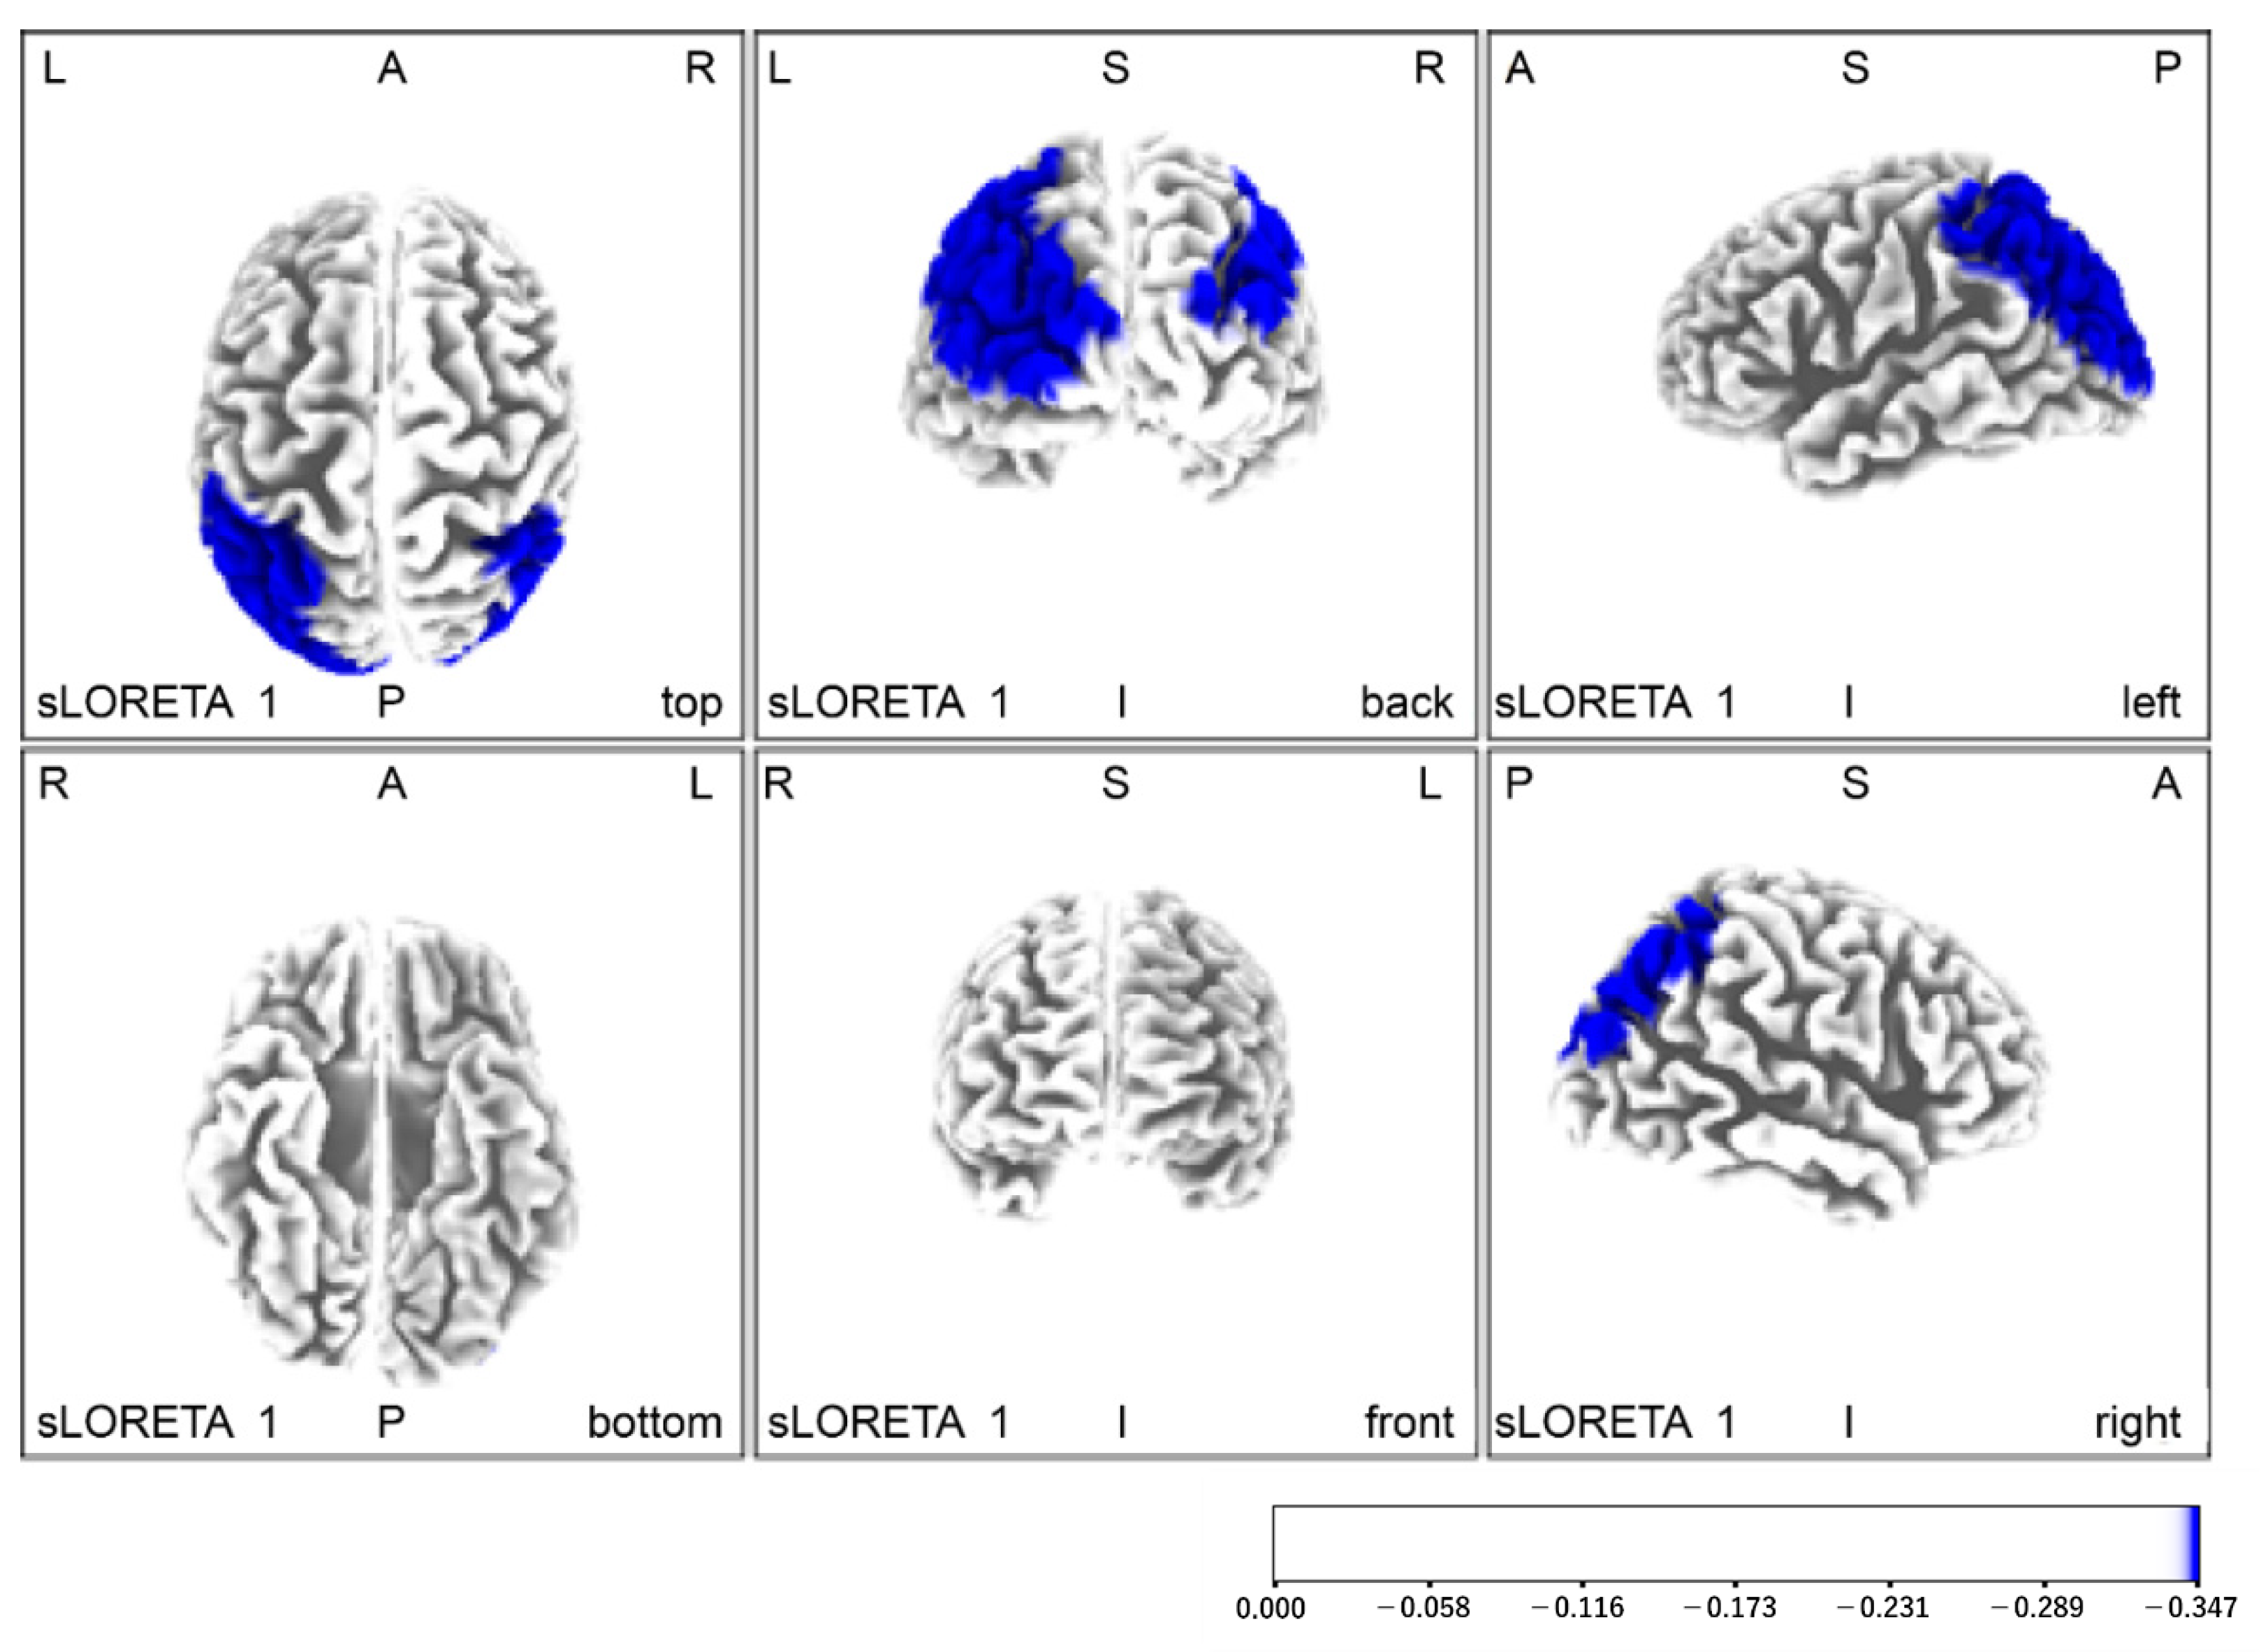

| Without Yubi-Recorder (red) vs. With Yubi-Recorder (blue) | |||||||

| Red | −25 | 40 | 45 | Left anterior cephalic lobe | Anterior cephalic eye field | 8 | 0.13 |

| Blue | −30 | −85 | 40 | Left posterior cephalic lobe | Visual field | 19 | 6.75 |

| Pre-intervention (red) < Post-intervention (blue) | |||||||

| blue | −40 | −55 | 60 | Left parietal lobe | supramarginal gyrus | 40 | 6.76 |